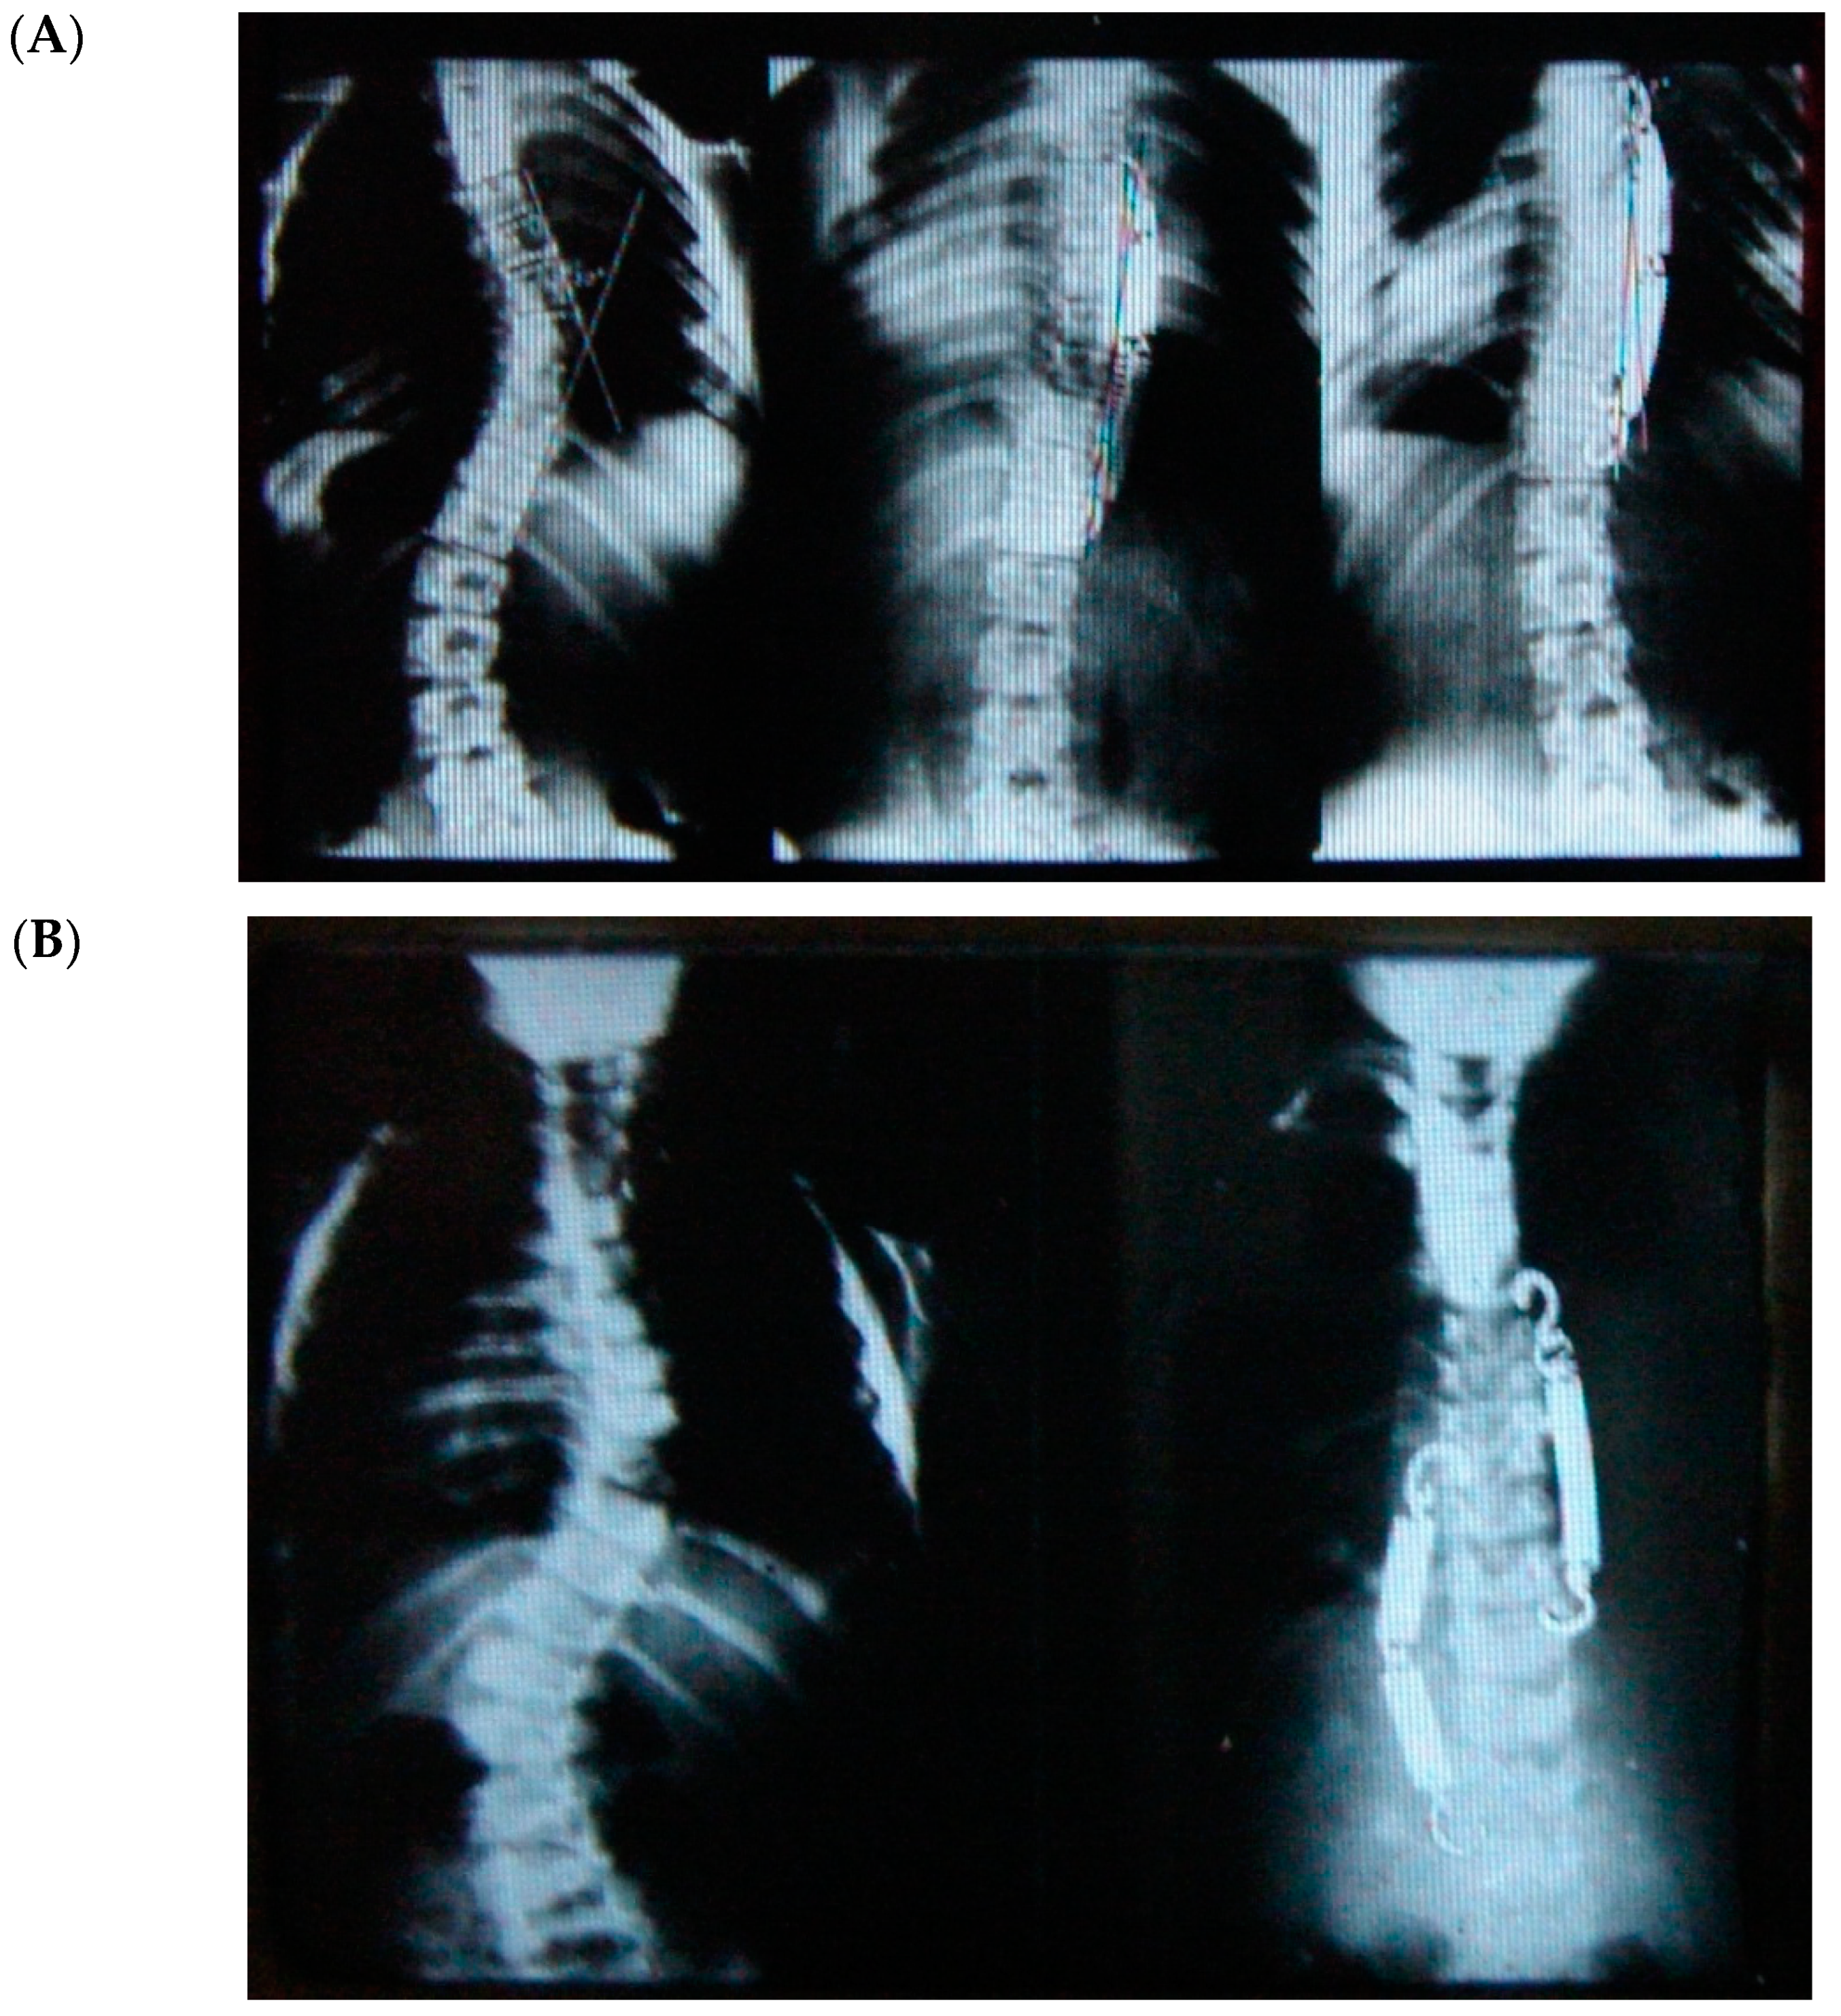

Correction of two (scoliosis and hypokyphosis) of the three plane deformities in scoliosis has already been explained, but how rotational correction happens in these growth-friendly procedures is not clear. We know that with the progression of scoliosis, the rotation of the vertebral bodies towards the concavity increases due to the imbalance/disturbance of the different growth plates and synchondrosis in the growing spine. Tethering, either anterior or posterior, on the convexity of the curvature locks this progressive abnormal rotation and may allow the opposite side to de-rotate the vertebrae gradually with growth, thereby improving the rotational deformity and the rib hump, as shown (Figure 2).

Figure 2.

Radiological regression of rib hump with decrease of the prominent ribs.